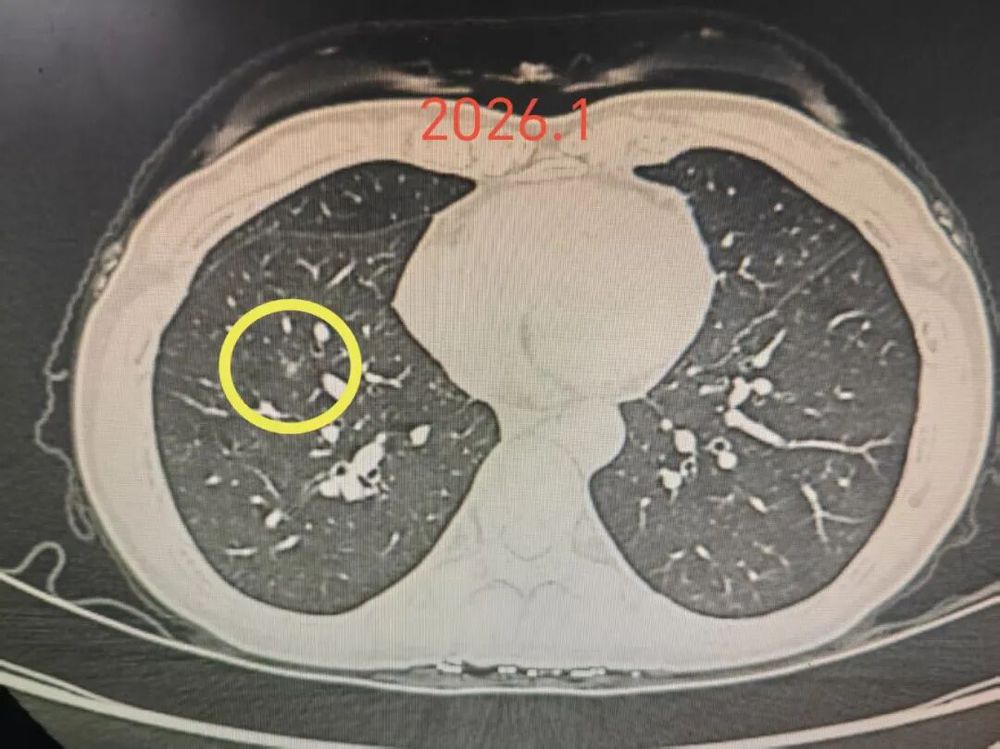

右下病灶C于2026年1月份复查时仍与2023年4月术前时几乎没有变化,考虑腺体前驱病变,仍可再随访。